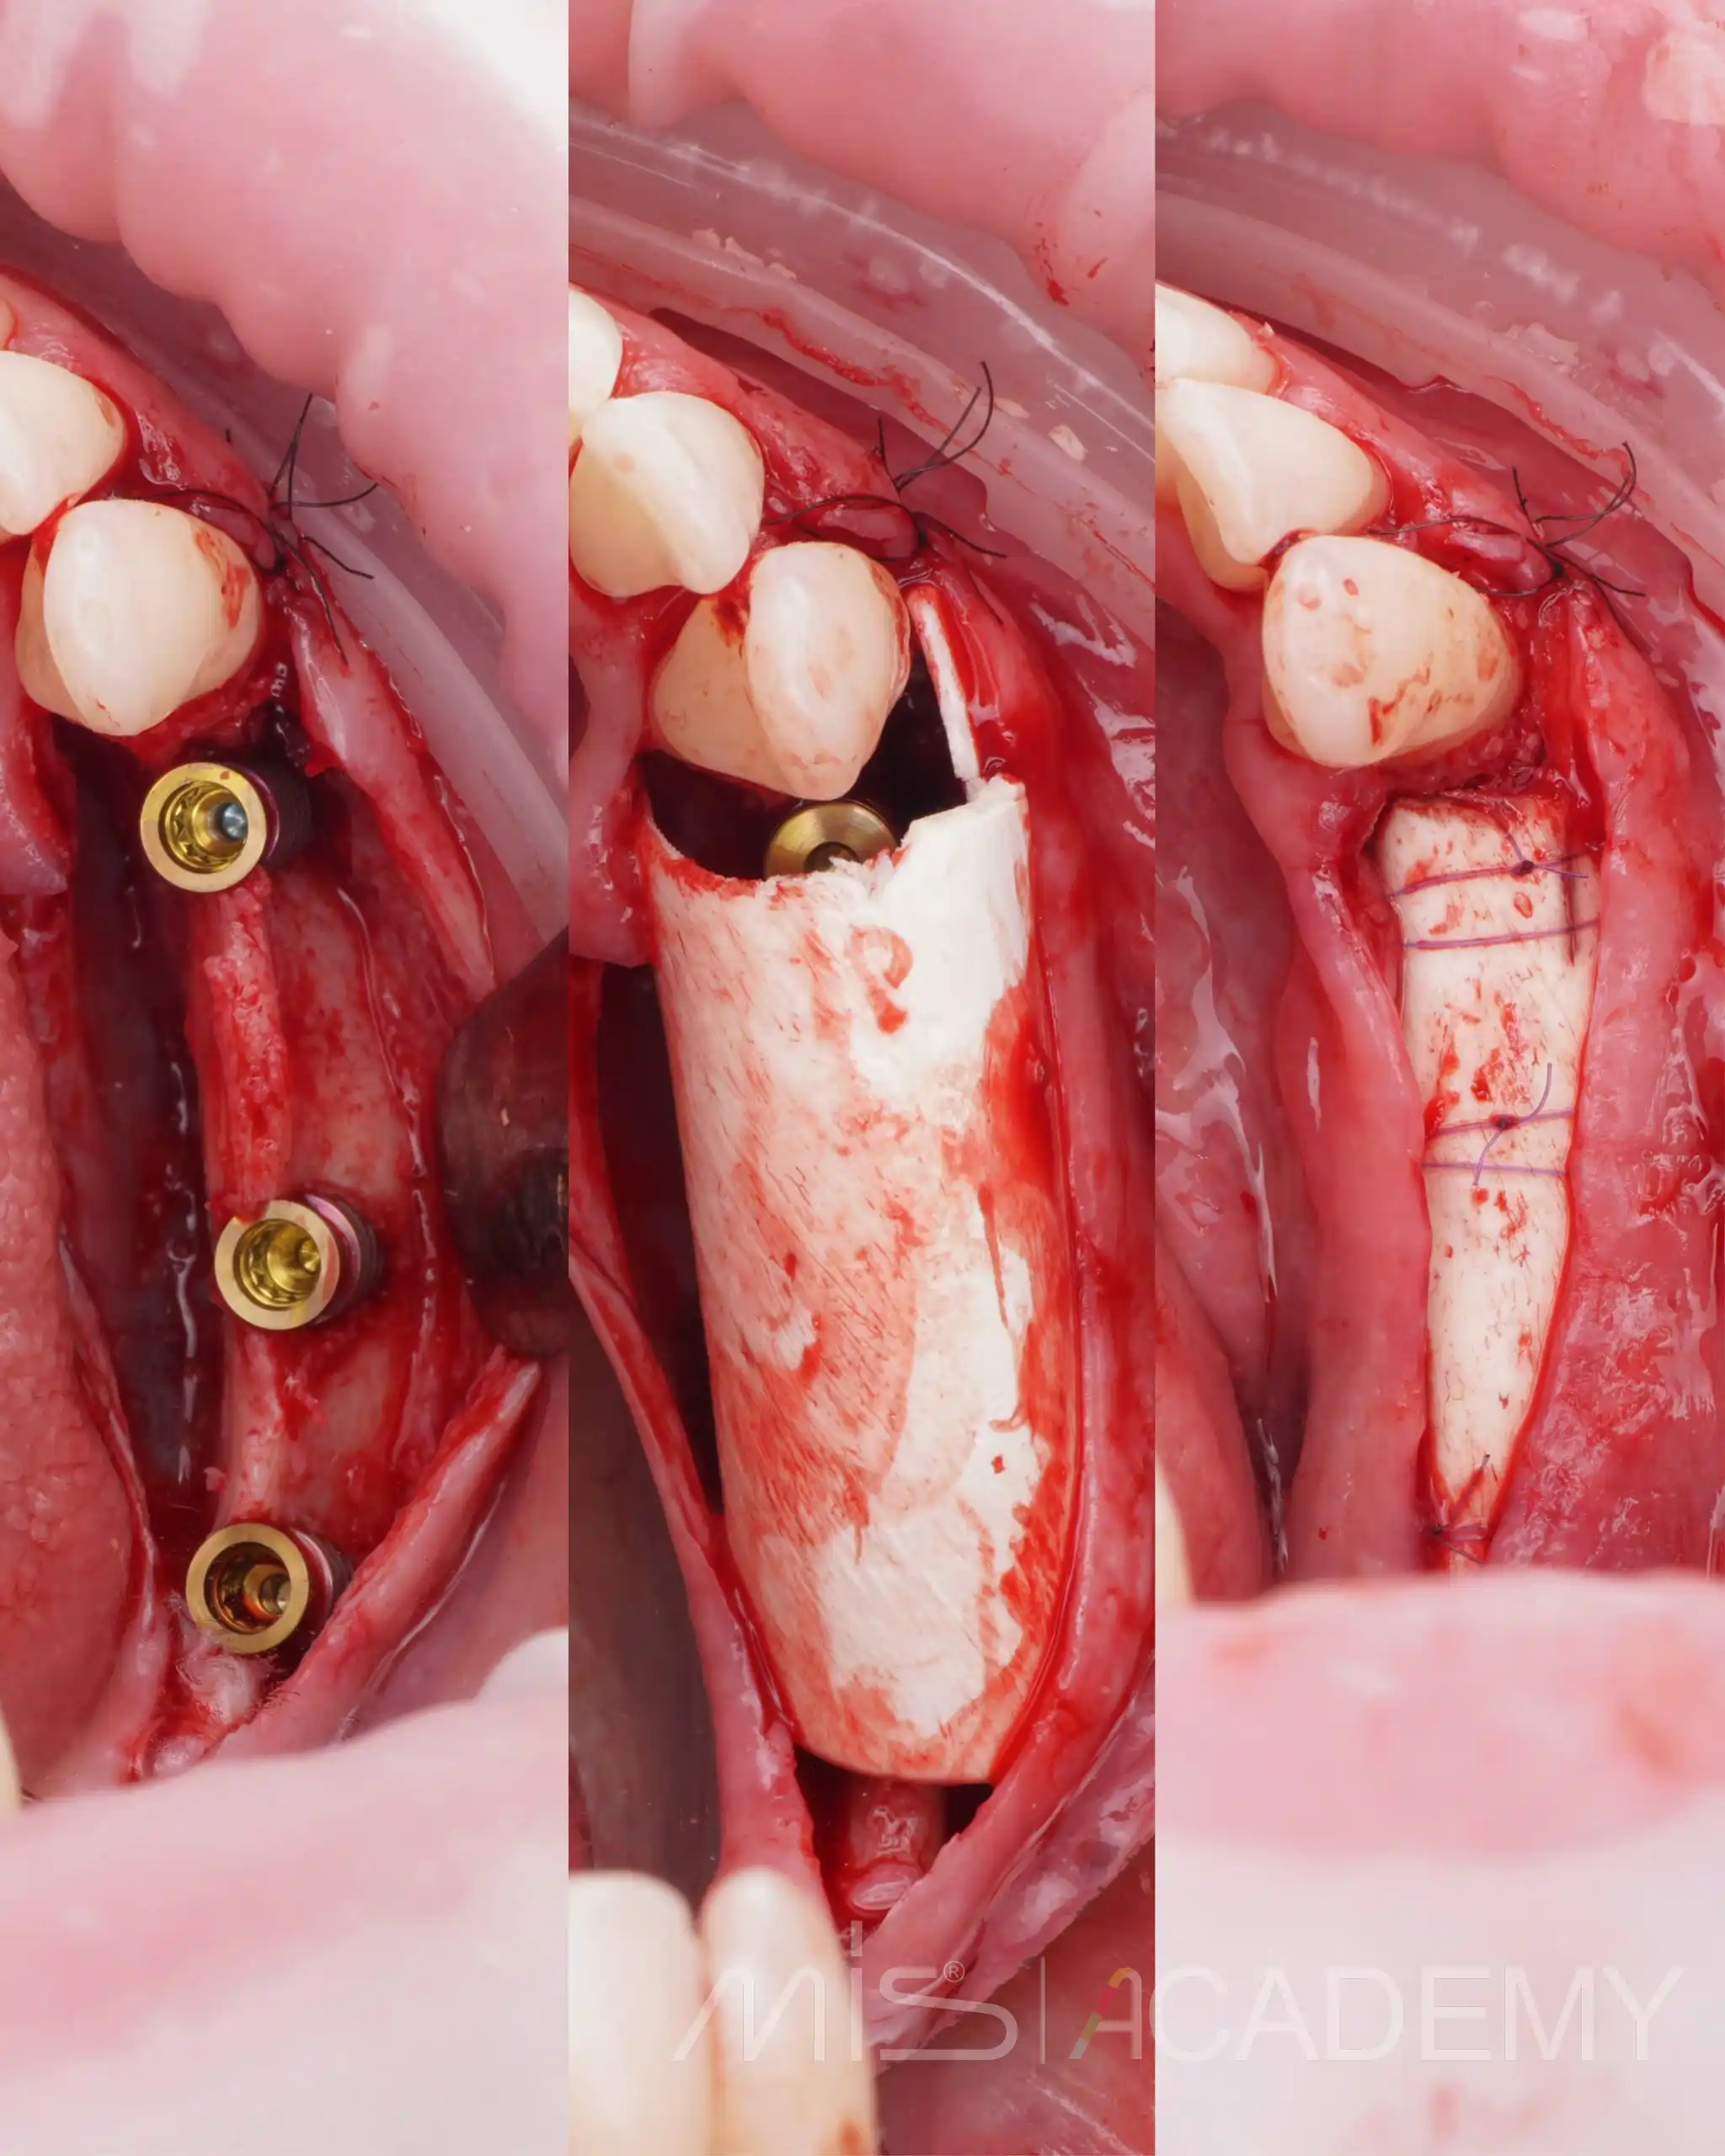

В боковых отделах выраженная атрофия по ширине и высоте. При планировании приняли решение об имплантации с одновременной костной аугментацией по ширине.

— Установлены имплантаты MIS C1.

— Connect абатменты с заглушками, которые дополнительно сработали как тенты.

— Костная пластика материалами Osteobiol: справа ксено MP3 с Derma, слева Gen-Os с нативным коллагеном и Lamina Curved, ушивание.